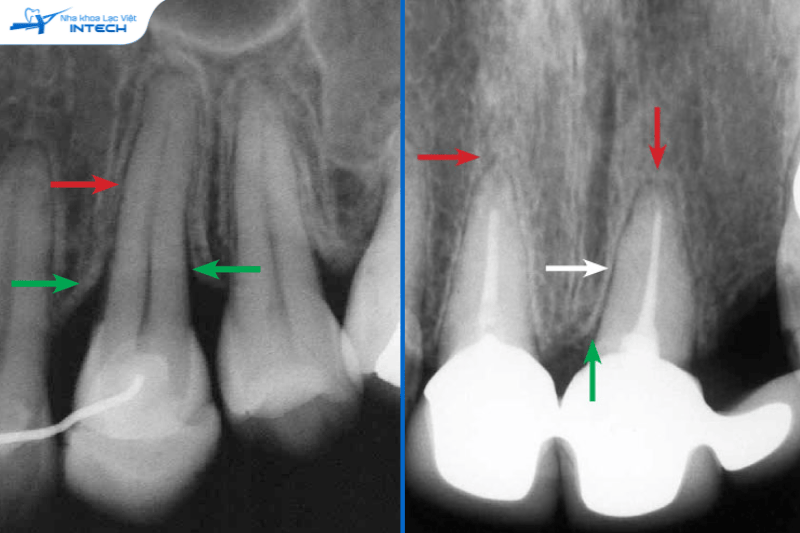

2. Biến chứng niềng răng: Tiêu ngót chân răng

Niềng răng có nguy hiểm không? Có, nếu xảy ra tình trạng tiêu ngót chân răng quá mức. Thông thường, khoảng 90% các trường hợp niềng răng sẽ có một chút tiêu ngót nhẹ ở chóp răng, chỉ khoảng 1-2mm. Đây là hiện tượng bình thường. Tuy nhiên, nếu bác sĩ dùng lực quá mạnh, chân răng có thể bị tiêu đi một đoạn lớn. Điều này sẽ ảnh hưởng nghiêm trọng đến tuổi thọ của răng.

tiêu ngọt chân răng khi niềng

Hầu hết các trường hợp niềng răng đều có thể bị tiêu ngót chân răng nhưng với mức độ nhất định

Dấu hiệu sớm của tình trạng này là răng bị lung lay quá mức. Mặc dù răng thường lung lay nhẹ trong quá trình niềng, nhưng nếu bạn cảm thấy đau nhức liên tục hoặc khi ấn vào thấy răng bị nhún, hãy nghi ngờ đến tác hại của niềng răng này. Để chẩn đoán chắc chắn, bác sĩ sẽ so sánh phim X-quang toàn hàm (Panorama) hoặc phim CT Cone Beam trước và sau khi niềng để đánh giá mức độ tiêu ngót.

3. Biến chứng niềng răng: Tiêu xương ổ răng

Xương ổ răng là nền móng vững chắc giúp răng đứng vững. Tác hại của niềng răng sai cách có thể làm phần xương này bị tiêu dần. Nguyên nhân của biến chứng  có thể do bác sĩ dùng lực quá mạnh, sai phương thức truyền lực, hoặc do bệnh nhân vệ sinh răng miệng kém dẫn đến viêm nha chu.

Dấu hiệu nhận biết tiêu xương ổ răng khi niềng

Tiêu xương ổ răng là một biến chứng diễn ra thầm lặng, khó nhận biết bằng mắt thường. Dấu hiệu ban đầu thường là răng bị lung lay nhẹ. Để chẩn đoán chính xác, bác sĩ sẽ cần chụp phim X-quang hoặc CT để kiểm tra mật độ xương và chiều cao xương ổ răng.